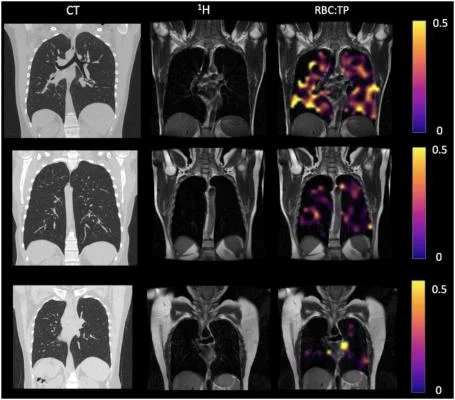

Пример КТ, протонная, протонная и эритроцитная визуализация: TP у участников, перенесших COVID-19. Верхний ряд — участник с RBC:TP = 0,49, средний ряд — участник с RBC:TP = 0,31, а нижний ряд — участник с RBC:TP = 0,24. Визуализация показала незначительные или отсутствующие заметные повреждения на КТ, но при этом очень гетерогенные и низкие RBC: TP в легких у негоспитализированных участников с состоянием после Covid-19. RBC:TP = отношение гиперполяризованного 129Xenon MRI легких спектрального пика эритроцитов к спектральному пику тканевой фазы. Изображение предоставлено Радиологическим обществом Северной Америки.

Участникам были проведены КТ грудной клетки, Hp-XeMRI, тесты функции лёгких, одноминутные тесты в положении сидя и стоя и опросники по одышке. Субъекты контрольной группы прошли только HP-XeMRI. КТ-сканы были проанализированы на предмет тяжести заболевания лёгких после COVID с использованием ранее опубликованной системы оценки и моделирования полномасштабной сети дыхательных путей (FAN). В анализе использовались групповые и парные сравнения между участниками и контролем, а также корреляции между клиническими данными участников и данными визуализации. Участники NHLC и PHC имели нормальные или почти нормальные КТ.

«Мы увидели, что способность газа переходить из лёгких в кровоток была меньше у пациентов, не госпитализированных по сравнению с госпитализированными с COVID», — сказал доктор Глисон. «Кроме того, обе группы участников имели более низкие значения Hp-XeMRI в растворенной фазе, чем здоровые участники, что указывает на потенциальные дефекты либо в слизистой оболочке лёгких, либо в окружающих кровеносных сосудах».

Результаты показали, что существуют значительные различия в среднем соотношении эритроцитов и тканевой плазмы между здоровым контролем и участниками PHC/NHLC, что указывает на потенциальные различия в функции лёгких.